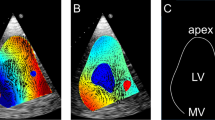

Echocardiographic Image Acquisition

For flow visualization purposes, B-mode echocardiography images of the left ventricle in long-axis view were acquired (Philips iE33, X5-1 xMatrix probe, Philips Electronics N.V., Bothell, WA, US). Measurements were performed by placing the echo-probe either on the sagittal portion of the left atrium or on the lateral surface of the right heart. By using the atrial approach, the required width of the echo-images was generally narrower, and therefore, the maximum frame rate in this view was higher. To enhance the visualized sector with a minimum number of sweeping lines, a thin-walled fluid-filled silicone pouch was used to increase the distance between the echoprobe and the epicardial wall. Additionally, the silicone pouch improved contact with the atrial wall as it partially compensated for the motion of the atrial contraction. With the resultant small sector angle, it was possible to capture the whole left ventricle with a high frame rate of 99 to 137 Hz. High frame rates are vital for capturing the high velocity magnitudes present since the displacement of the microbubbles must be small enough that they remain within the same PIV interrogation region of an image pair.

A microbubble solution was injected into the preload reservoir, from where it was immediately transported into the left ventricle and visualized in the B-mode images (Fig. 2). The microbubbles were created by forcefully agitating saline and air (5–10 vol% air) between two syringes connected with a three-way stopcock for at least five times 5,16,26,35 until the solution became partly opaque and white. For each heart, B-mode sequences in DICOM format were recorded for an unsupported, partial, and full support condition.

Echo PIV

The B-mode images were analyzed using a previously validated iterative PIV algorithm.18,41 The algorithm consisted of two stages: First, a region of interest was selected in the LV outflow tract and a simple 2D cross-correlation was applied on this region for all image pairs from 3 cardiac cycles. This cross-correlation was used to give a rough estimate for the velocity magnitude in that region, which also provided a periodic signal with the same periodicity as the cardiac cycle. This signal was used to split the echo data into single cardiac cycles, align those cycles, and set up data bins for each 1/50th phase of a cardiac cycle. Based on preliminary evaluations, the use of three consecutive cardiac cycles was found to be sufficient. Further, even in case of arrhythmia it was possible to record three consecutive beats with the same duration in all experiments. The second stage was an iterative PIV algorithm which used all the image pairs within a single bin. Coarse regions of interest (48 by 48 pixels with 50% overlap) were first used to calculate cross-correlations which were then averaged. These averaged cross-correlations gave a rough vector field, that was used to apply a displacement map to the locations of the finer regions of interest (24 by 24 pixels with 50% overlap) within the second image of each image pair such that the particles remained within the regions of interest. The final vector field consisted of 53 by 42 pixel maps with each region being approximately 3 by 3 mm depending on the field of view for the whole cardiac cycle.

Calibration of dimensions was based on the scaling factor (image resolution 800 by 600 pixels, spatial resolution 0.15–0.26 mm/px) in the DICOM data header. A sweep correction algorithm18 was additionally applied to compensate for errors resulting from the echo-image creation by sweeping the echo beam through the imaging plane.

The flow patterns for each different support level and experiment were visualized. The mean velocity flow field over one cardiac cycle (steady streaming analysis) was computed to identify general flow features. Further, velocities in the LVOT were quantified for each of the experiments. The normalized flow pulsatility in the LVOT was computed by the difference between the maximum and minimum velocity (vmax, vmin) normalized over the mean velocity (vmean, Eq. 1) to compensate for cardiac output variability across experiments.

In unsupported hearts, the following ventricular flow patterns were observed. In the early diastolic filling phase, a clockwise vortical structure was created by the mitral inflow starting at the LVOT (left column in Figs. 4 and 5). Until the end of the diastole, this vortical structure enlarged until it encompassed the entirety of the ventricular cross section. The diastolic mitral inflow was hence redirected towards the LVOT through this enlarged vortical flow structure that extended down to the apex in a clockwise direction. During systolic ejection through the aortic valve, peak velocities reached 0.50 (0.43–0.54) m/s and the vortical flow structure vanished. The mean velocity over the cardiac cycle in the LVOT was 0.08 (0.07–0.09) m/s (Table 2).

Marked differences were observed between the unsupported and partially supported ventricles (middle column in Figs. 4 and 5). The diastolic vortex formation, similar to the unsupported condition, formed in the LVOT during the early filling phase; However, the vortex enlarged to a lesser extent than in the unsupported heart due to the LVAD acting as a flow sink as it continuously drained blood from the apex. This reduced the size of the vortex such that it did not encompass the entire ventricular cross section. The peak velocities in the LVOT were significantly reduced compared to the unsupported situation (mean 0.06 (0.01–0.07) m/s and peak 0.27 (0.07–0.47) m/s) (Table 2).

During full support (right column in Figs. 4 and 5), the aortic valve was continuously closed and the physiologic vortical formation and flow structures were absent. Although clockwise vortical structures were formed towards the end of diastole in the LVOT, they did not encompass the entire ventricular cross section. The velocities in the LVOT were considerably lower (mean velocity 0.03 (0.02–0.06) m/s and peak velocity 0.14 (0.06–0.17) m/s) compared to the partial support condition. Due to the closed AV during the entire heart cycle, the pulsatility during the heart cycle was significantly reduced compared to the partial support condition. A detailed comparison of velocities and pulsatility in the LVOT is provided in Table 2.